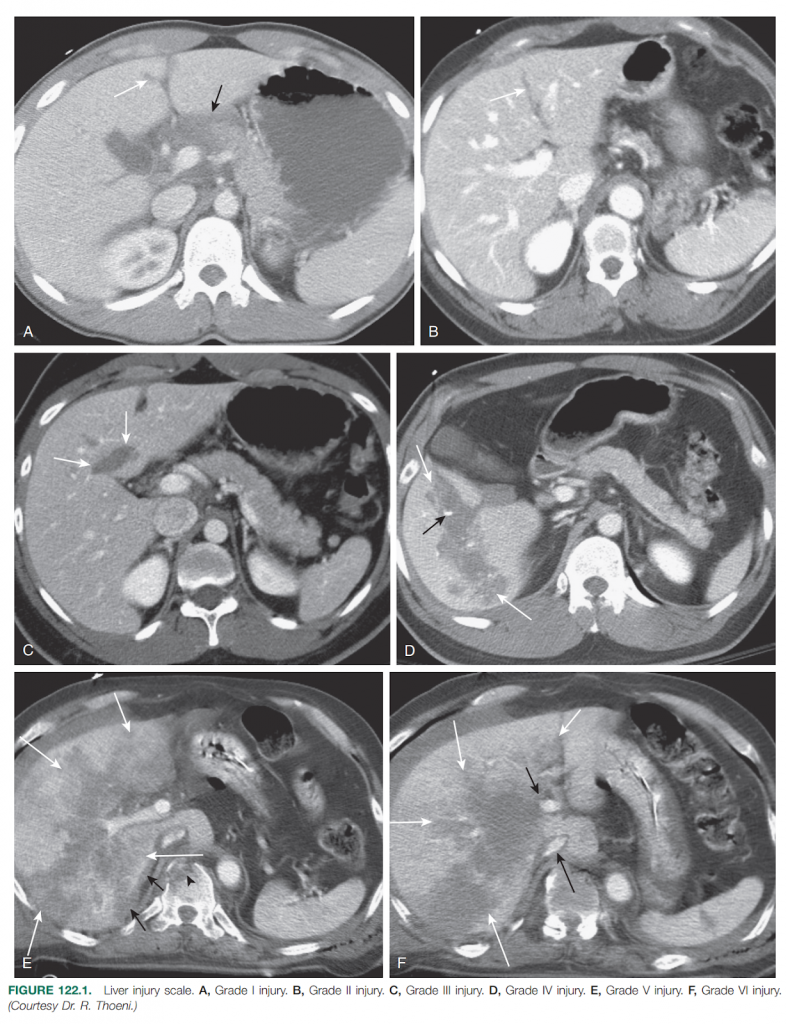

Hình 1. Hình ảnh chấn thương gan trên phim chụp CT

A, Độ I. B, Độ II. C, Độ III. D, Độ IV. E, Độ V. F, Độ VI